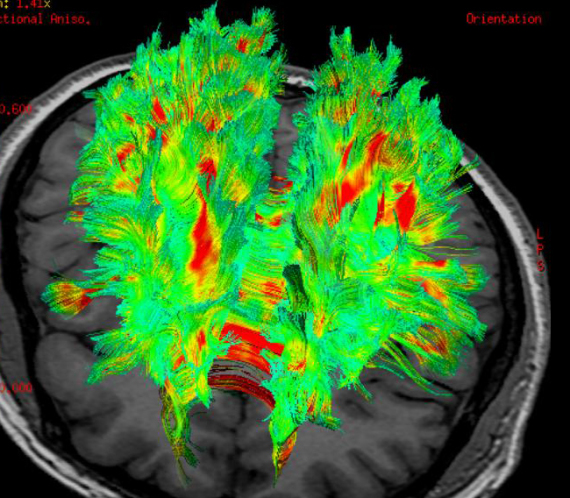

研究还发现,最终活下来的53名患者中,近四成在接受心肺复苏术时脑电图恢复正常或接近正常,其中甚至包括已经接受抢救一小时的患者。

报告主要作者之一、兰贡医疗中心重症监护医生萨姆·帕尔尼亚说:“尽管医生们一直认为,心脏停止向大脑供氧约10分钟后,大脑就会遭受永久性损伤,但我们的研究发现,在持续进行心肺复苏术相当长时间后,大脑仍能显示出电信号恢复的迹象。”